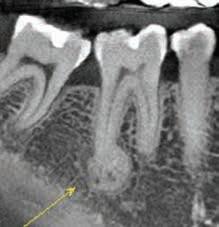

2-Dimensional Radiography

The use of intraoral periapical (PA) and bite-wing radiographs to detect CEJ and alveolar bone levels has been reported.20,21 They also serve as tools aiding in the diagnosis and treatment planning of APE cases.22 Zanatta and colleagues compared the accuracy of PA and bite-wing radiographs and TGP in the planning of crown lengthening procedures with the DBL measurement.23 All methods had statistically significant differences and were inferior in accuracy compared with the reference standard. Measurements obtained via TGP were the closest in accuracy compared with the reference standard, followed by bite-wing radiograph. PA radiographs were the least accurate among the methods investigated.23

Cone-Beam Computed Tomography

Cone-beam computed tomography (CBCT) has become an essential tool in the field of dentistry, as it offers a highquality, 3-dimensional (3D) image.25 It is superior to bone sounding and conventional 2-dimensional radiography in the assessment of CEJ and bone morphology, as well as detecting abnormal root anatomy and bony dehiscence or fenestrations.13 Furthermore, it is more comfortable for patients and less invasive than bone sounding.26 Leung and colleagues reported on the greater accuracy of CBCT in identifying the CEJ than identifying alveolar bone margin.26 This was due to the fact that the CEJ is the junction between enamel and cementum, which have different densities, and the latter is the interface between cementum and bone, which have similar densities. In addition, greater accuracy was reported in detecting bone fenestration than dehiscence.

Grimard and colleagues reported a strong correlation between CBCT and direct surgical measurements of the hard tissues.27 Although CBCT was found to underestimate the distance from CEJ to the base of bone defect, it precisely estimated the distance between CEJ and alveolar crest. In contrast, intraoral PA radiographs were found to be less reliable than CBCT, as they underestimated the measurements of all investigated parameters considerably.27 Batista and colleagues suggested the use of CBCT for the diagnosis and presurgical planning of APE cases, as it provides accurate measurements related to the CEJ and alveolar bone crest, in addition to the actual anatomic crown length.4